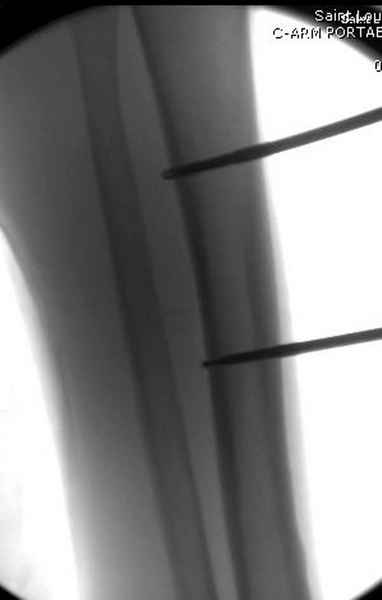

Больному с политравмой установлен наружный "spanning-bridging" фиксатор, после нескольких Irrigation&Debridment на фоне отрицательного посева из раны, через открытый участок установлен 4.5 mm Locking Plate.

На фоне фиксированного перелома бедра мероприятия по восстановлению мягкотканого покрова. Перелом голени зафиксирован после стабилизации бедра традиционным методом.

Хирургическую обработку надо повторить неоднократно до очищения раны. Фиксатор типа "бедро-голень" помогает стабилизировать конечность и облегчит обслуживание.